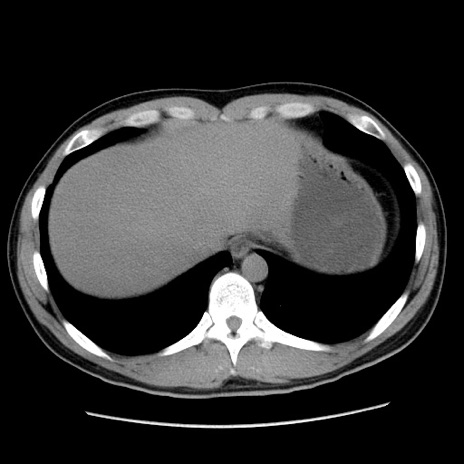

冠状断像

【症例】20歳代 男性

【主訴】心窩部痛

【現病歴】今朝より上腹部痛あり。一旦軽快していたが再度出現したため救急要請。昨日夕に白身の魚を含む刺身を食べた。

【身体所見】BP 136/89mmHg、HR 74/min、BT 37.0℃、腹部:膨満、軟、心窩部に圧痛あり。反跳痛なし、筋性防御なし、腸雑音やや亢進あり。

【データ】WBC 17700、CRP 0.48